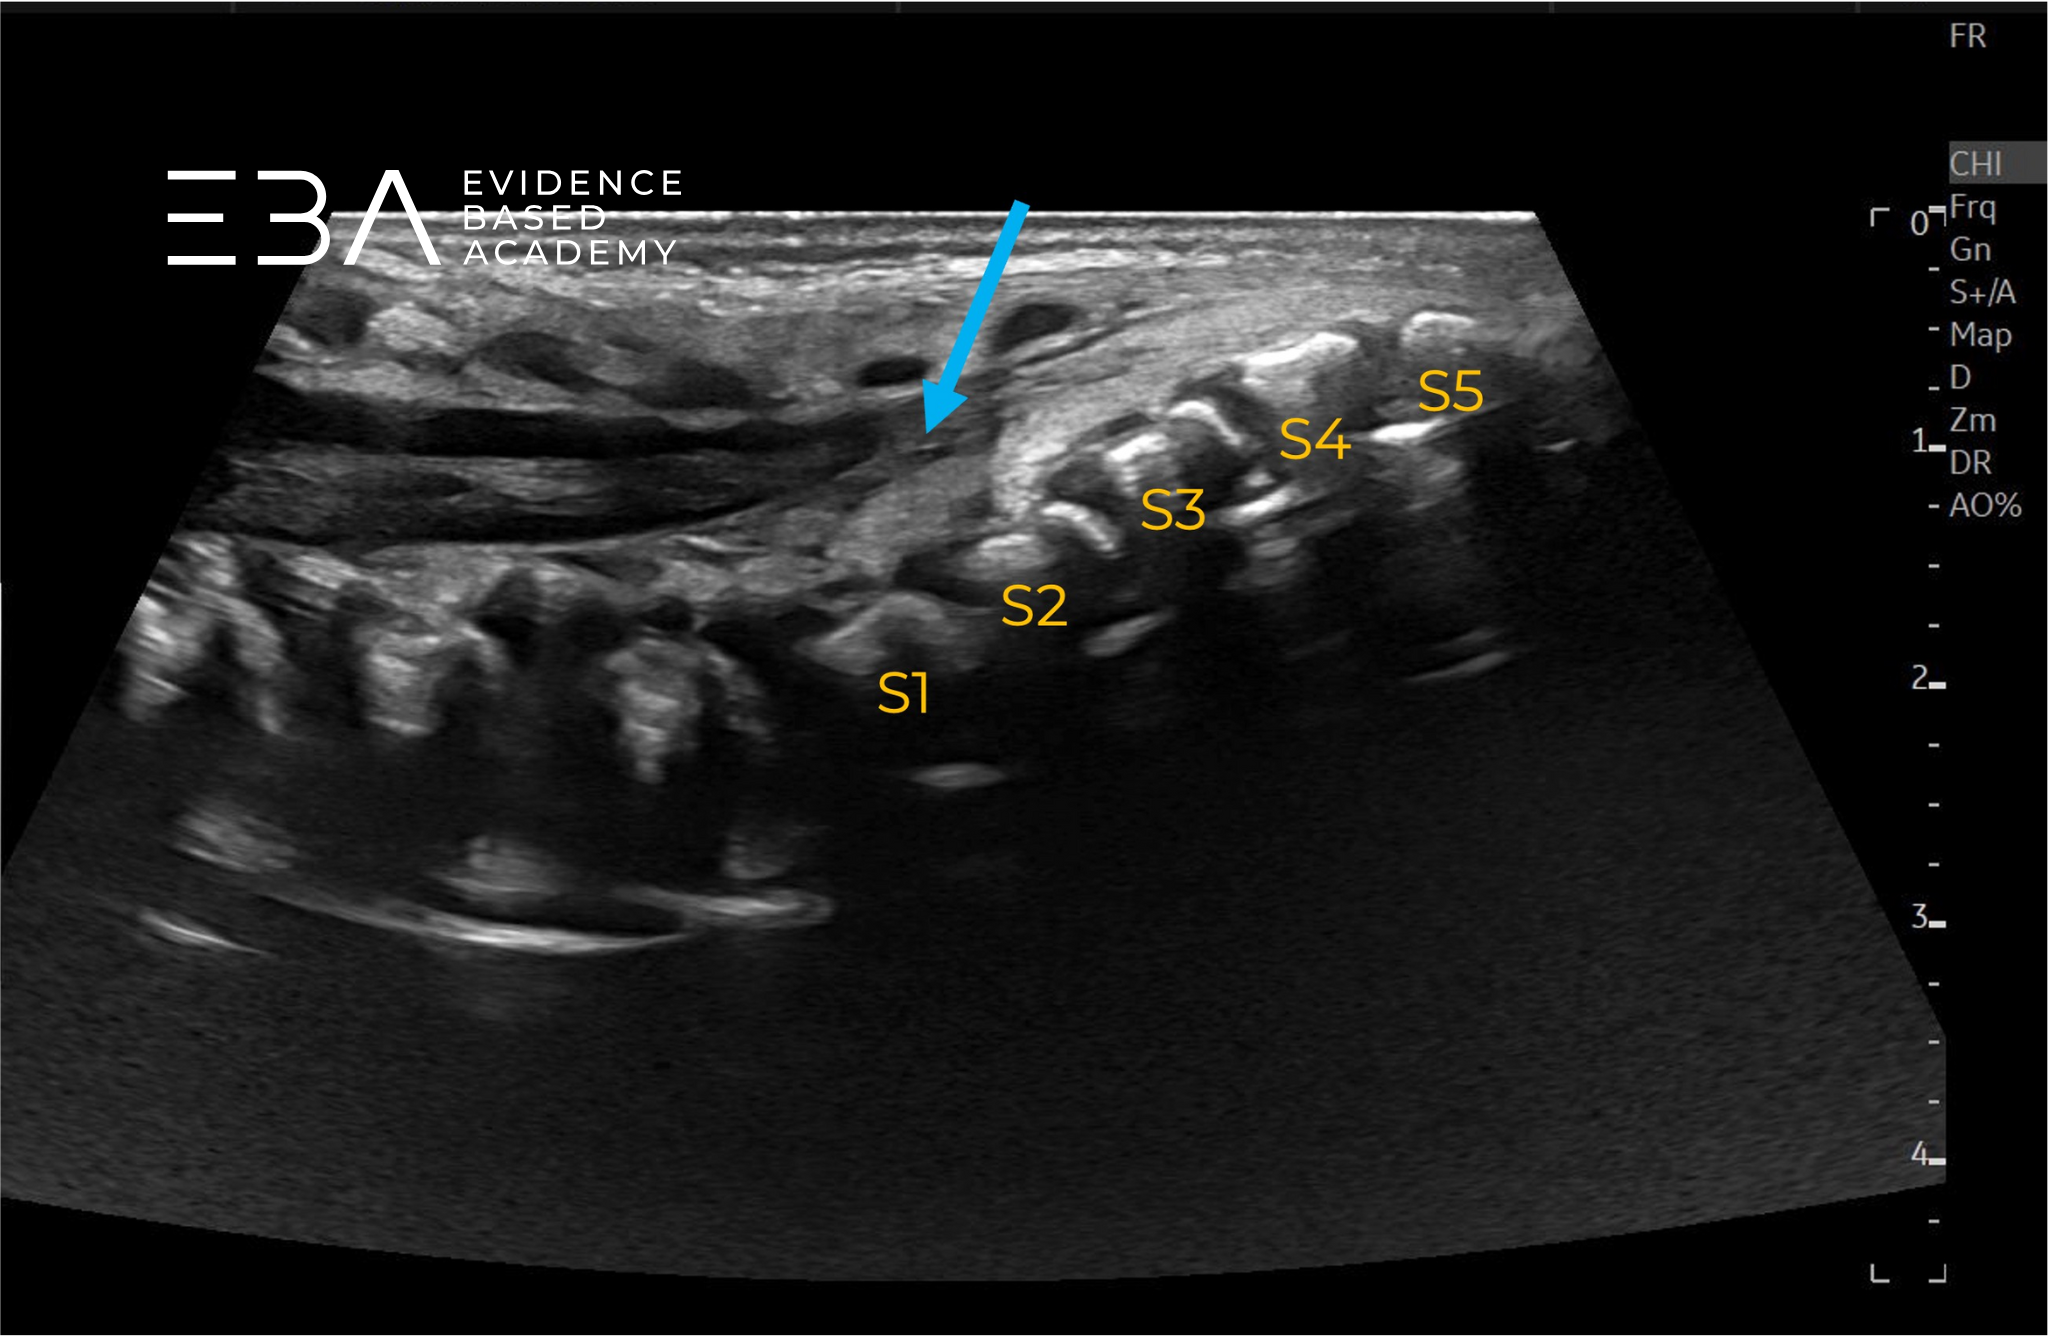

fot. 9

Przekrój podłużny kanału kręgowego – obrazowanie panoramiczne. Numeracja kręgów.